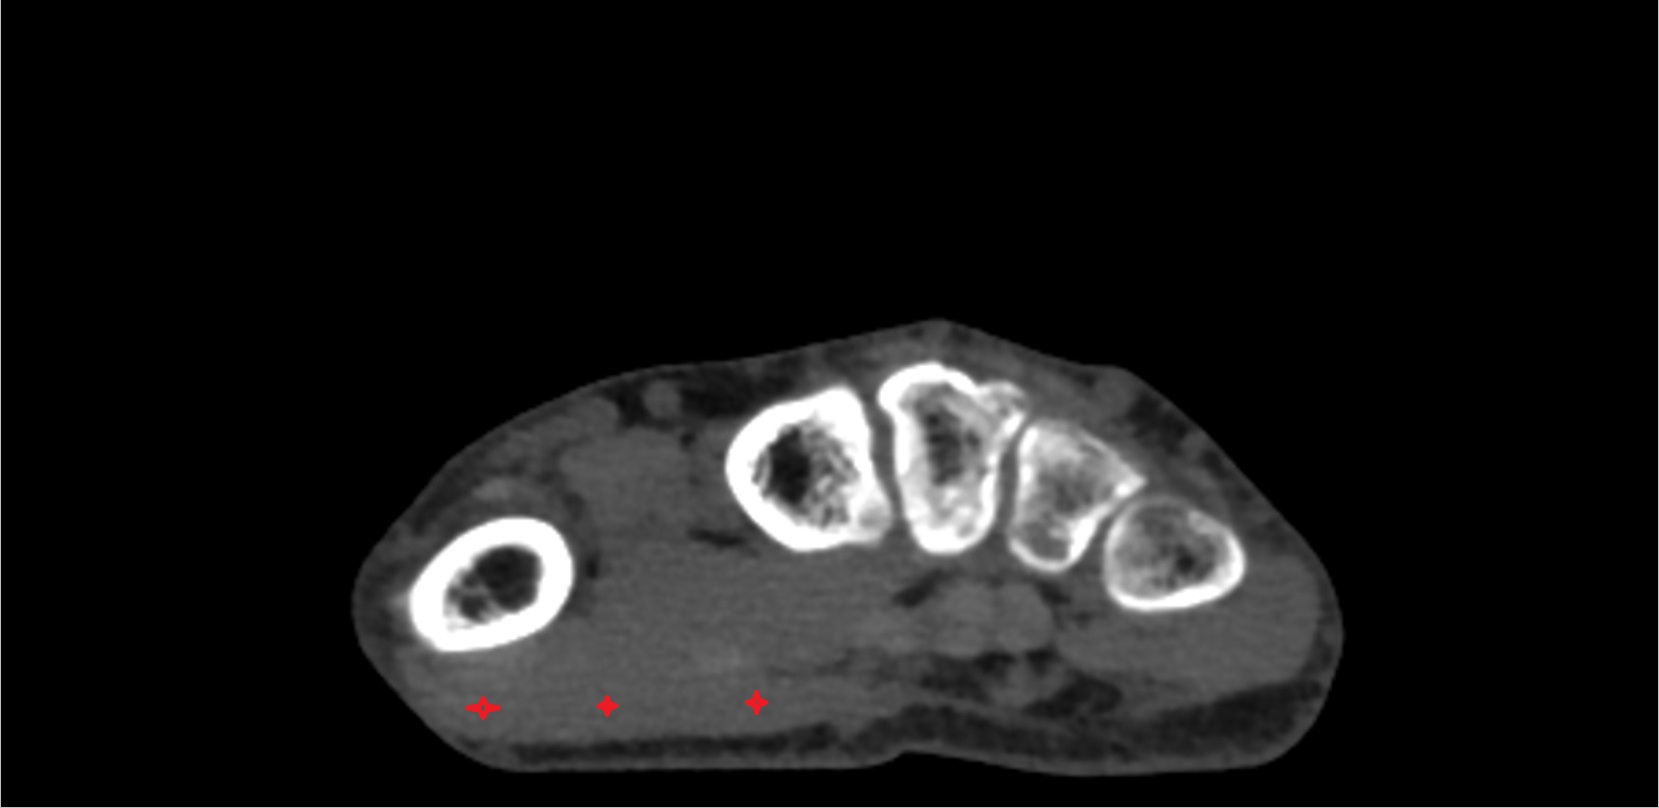

- Plantar aponeurosis